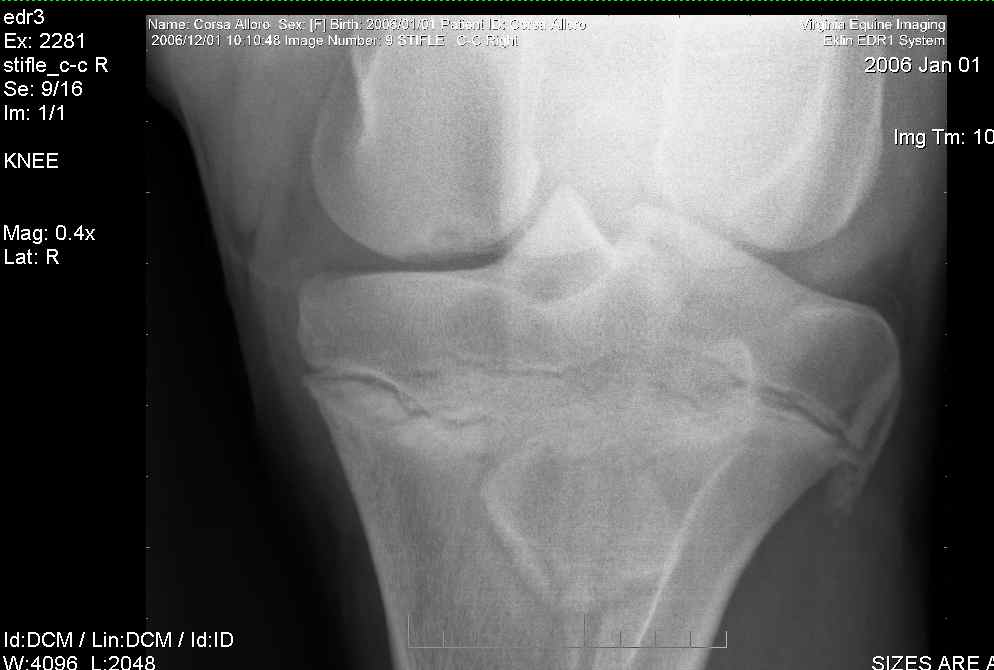

Right stifle-1

Right Stifle-2

Right Stifle-3

Right Stifle-4

I am sorry to meet you over such a serious problem. I am currently traveling so don't have access to my library where I might be able to provide you with more precise prognostic information but the OCD lesions on the trochlear ridges of both stifles are remarkable and often result in chronic lameness with secondary DJD of the stifles. Therefore surgery would be recommended and the prognosis from the radiographs alone would be guarded for future athletic potential but should really wait until the arthroscopic surgery when a better idea of the pathology in the joint can be better characterized. The horse should not be bred because of genetic predisposition for such lesions. Is there effusion (swelling) in the stifle yet?

This is how my vet explained the xrays to me: On the first xray, look at the top-left bone (femur). The bottom of it should have a smooth curve going all the way around, but the bottom of the femur shows up darker on the xray, and the edge is sheared off. This lesion is less dense (softer) than the rest of the bone. In surgery, they would take out the lesion (all of the damaged area), and fill it back in new material. The first 4 pics are her right stifle, the last three pics are her left stifle. On the first pic of her left stifle (fifth picture in the post) look at the bottom edge of the bone on the top right. Again, you can see the damaged edges. On the last pic, I think there is another area of OCD showing up on the top-right side. Maybe Dr. O. can better clarify the areas we are looking at if I am incorrect, or if I am missing anything else.